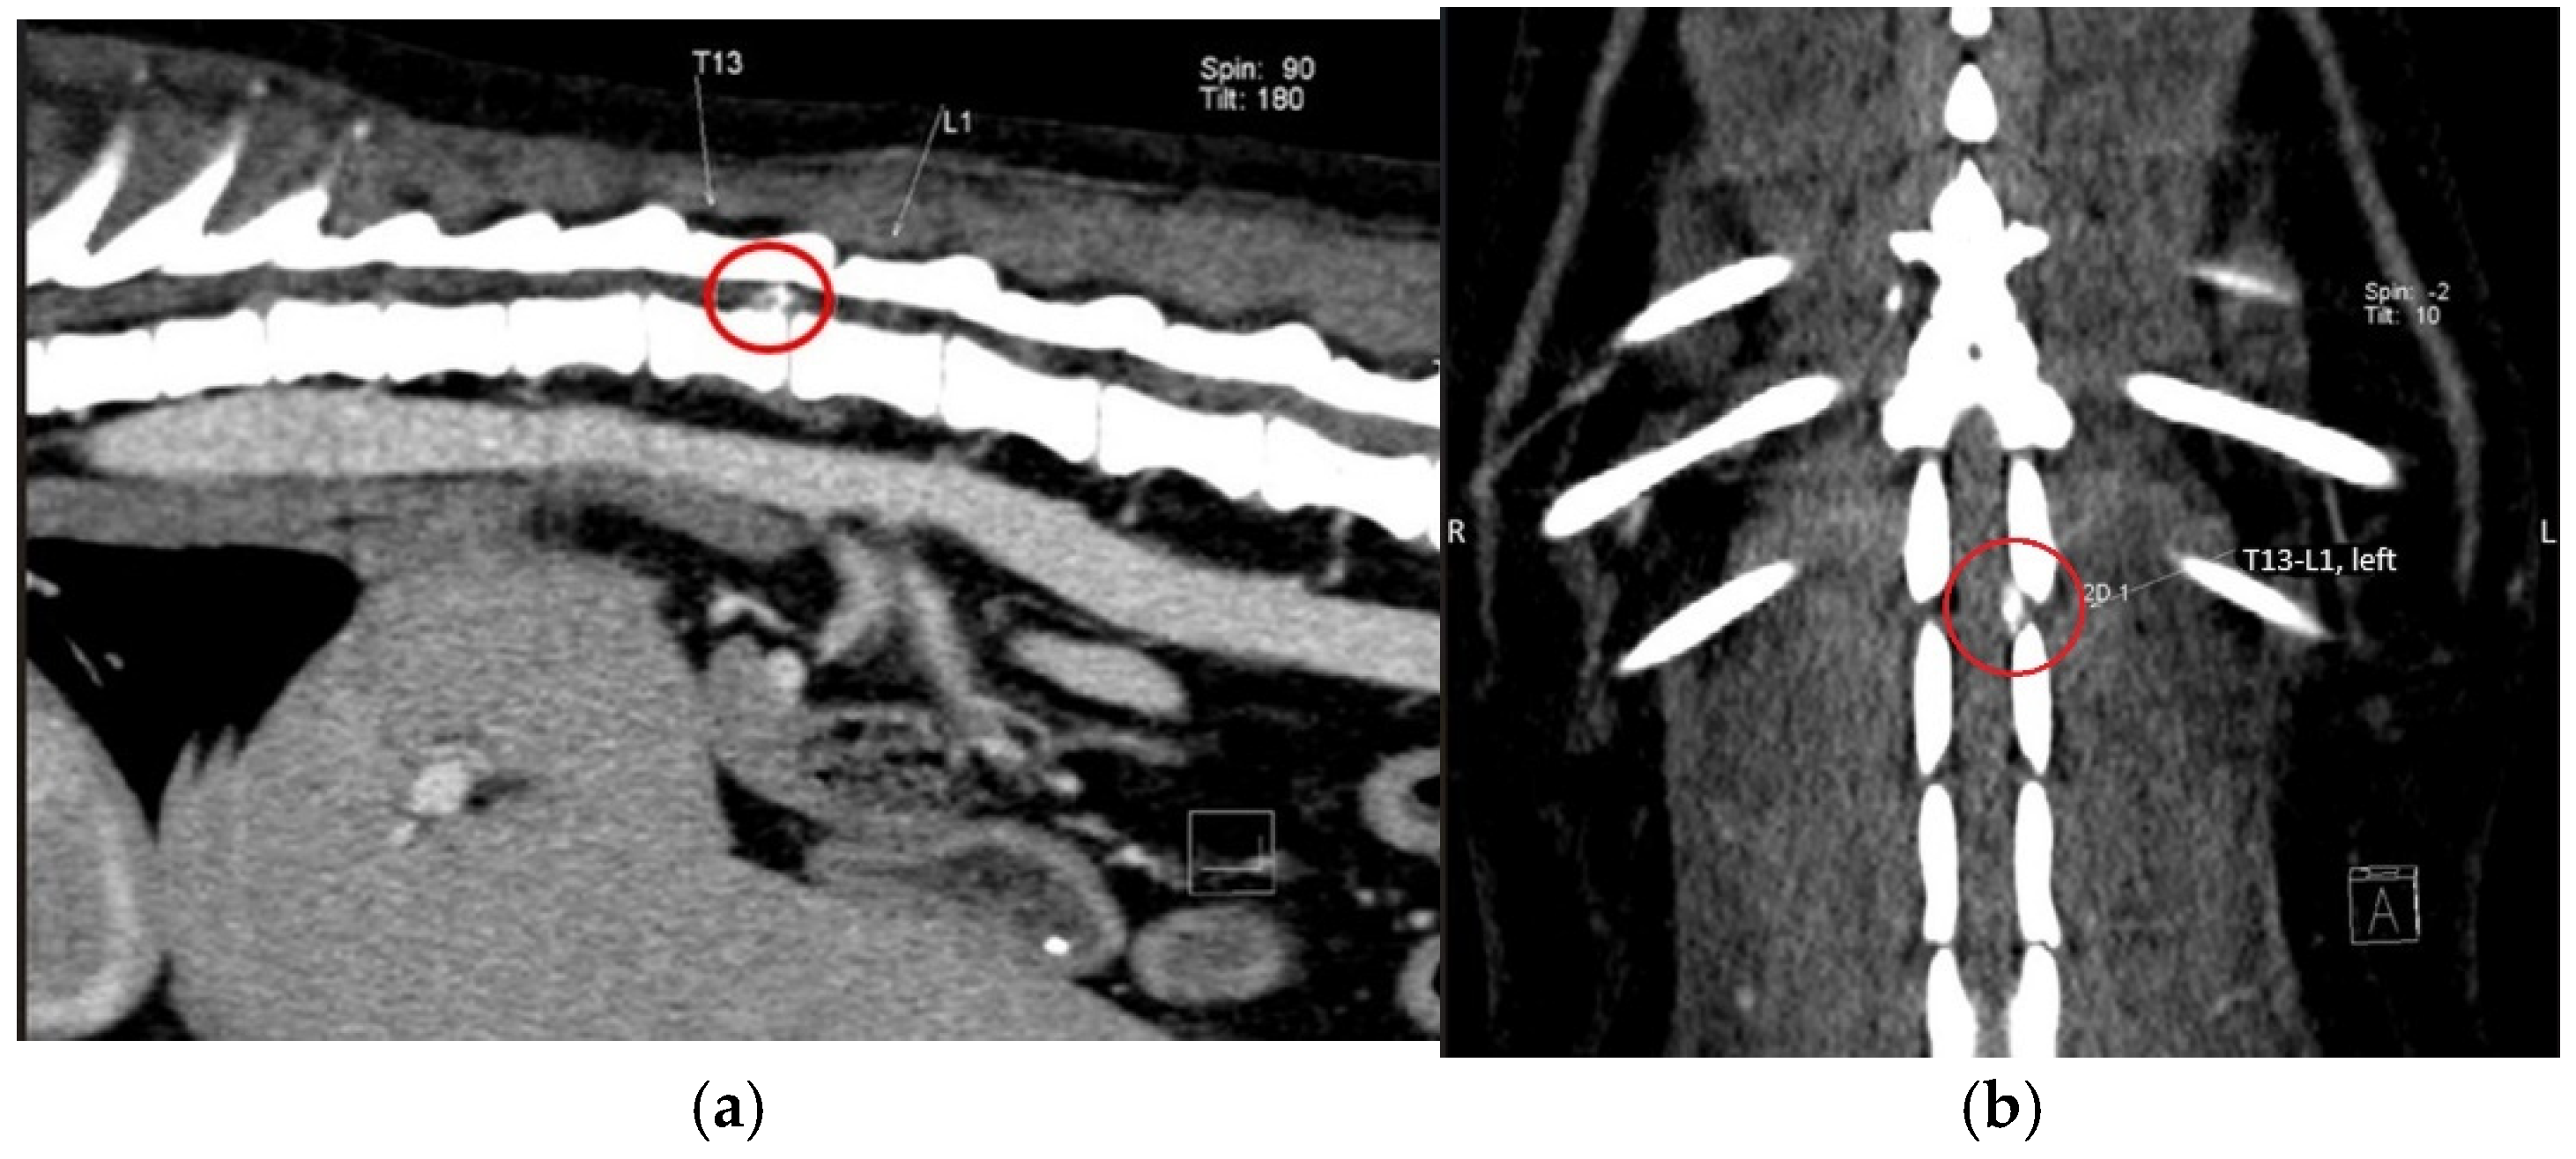

A total of 39 computed tomography scans were selected, and the results identified the following locations: four in the T11–T12 space, six in the T12–T13 space, 12 in the T13–L1 space (Figure 2a,b), six in the L1–L2 space, and four in the L2–L3 space. In nine cases, the disc material was located beneath the spinal cord, in 12 cases the disc material was identified with left lateralization, and, in 11 cases, the disc material was located on the right side. For seven conventional computed tomography scans, no disc extrusions were identified, and these cases were, therefore, excluded.

Figure 2.

Computed tomography image from a dog with T13–L1 disc extrusion: (a) sagitally reconstructed view of the vertebral column, T13—13th thoracic vertebra, L1—1th lumbar vertebra, (b) dorsally reconstructed view of the vertebral column, T13—13th thoracic vertebra, L1—1th lumbar vertebra, red circle—extruded discal material.